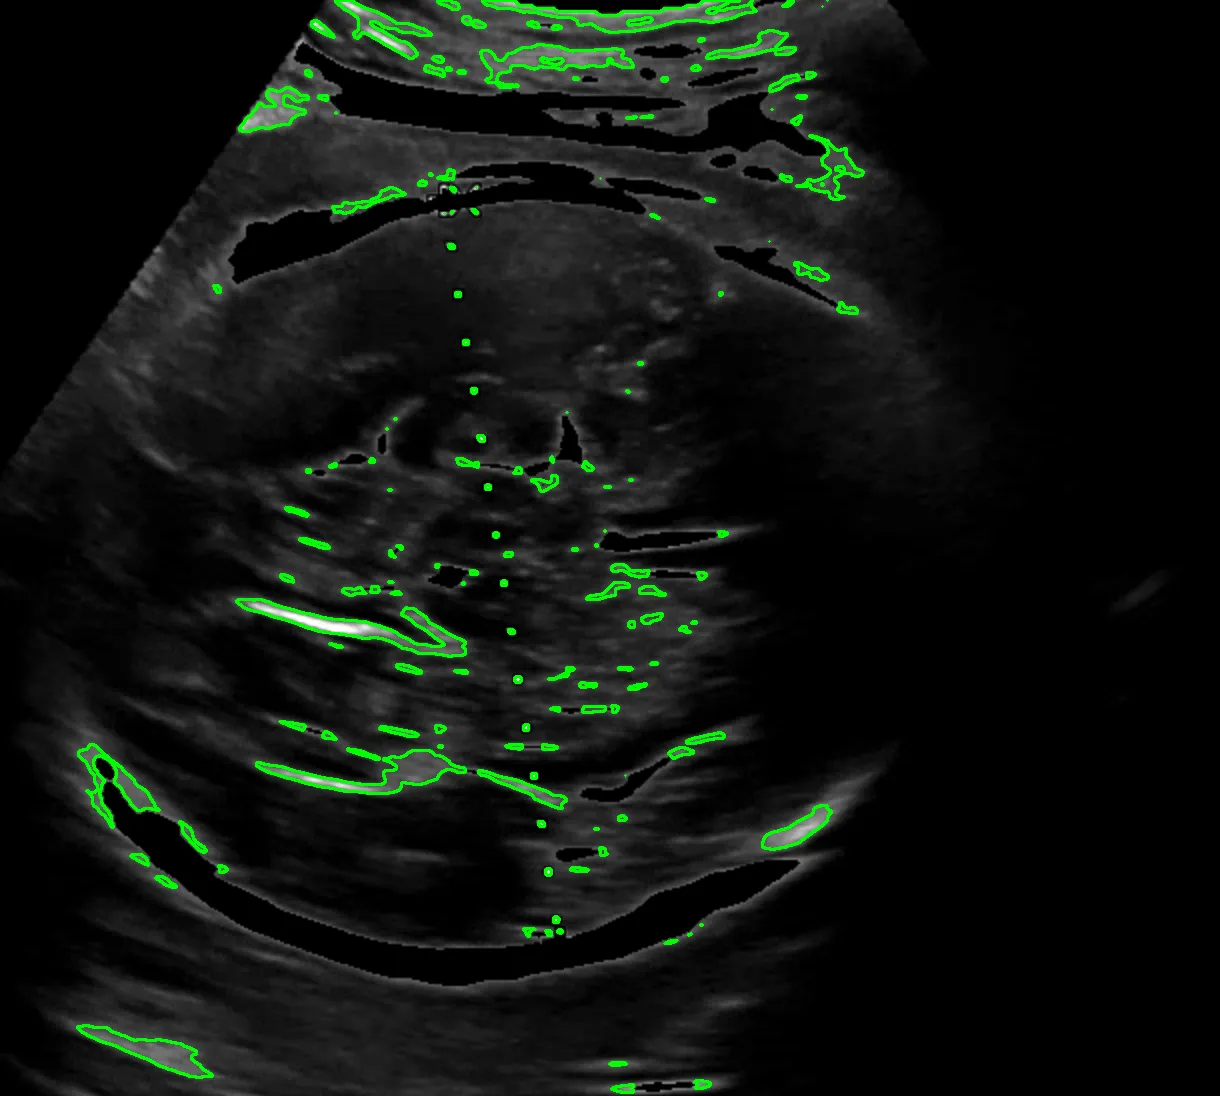

실제로는 8.22 cm 로 기록되었고 내가 측정한 기록값은 8.29 cm 로 오차는 크지 않았다. 가설을 검증했고 충분히 해볼 만하고 생각했다. 다만 아래와 같은 해결 과제가 남았다. 첫 번째는 계산 시 (14 cm / 스케일 바 픽셀 거리) 로 하드코딩해서 배율을 계산했기 때문에 스케일 바를 검출하는 이미지 전처리 과정이 필요했다. 두 번째는 초록색 영역 검출 시 곡선과 같은 형태 두 개를 찾고 그 사이 거리를 찾는 식이라 이미지별로 다소 편차가 있었다. 내 눈에는 원처럼 보이는데 컴퓨터가 인식할 때는 원으로 인식하지 않아서 반원 곡선 형태를 찾도록 코딩했다.

이미지 전처리 과정을 거쳐서 원하는 영역을 추출하도록 개선했다. 이미지 전 처리 과정이 잘 구축해두면 정확도가 높아진다. 이미지 전 처리 과정은 다음과 같다:

> (전처리)이미지를 선명하게 만들거나, 점선 원을 찾기 쉽게 테두리를 강조한다.

점선 원 찾기:

> 이미지에서 점선으로 이루어진 동그라미(원)을 검출한다.

> 원이 보이지 않으면 원의 크기를 키우거나 조건을 바꿔 여러 번 다시 시도한다.

원 주변 처리 (마스킹):

> 찾은 원을 기준으로 이미지를 잘라내고, 원 바깥부분은 지운다.

> 예를 들어, 원 안쪽만 남기고 나머지를 흐리게 처리할 수도 있다.